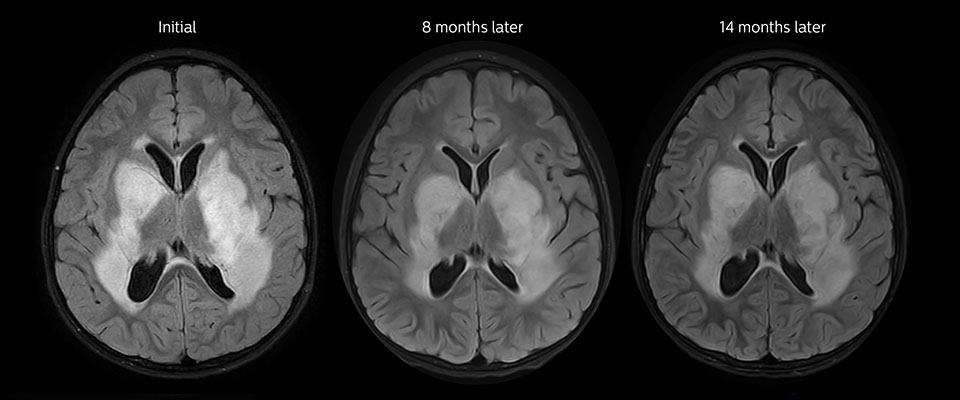

Niedrig differenziertes Gliom bei einem 5-jährigen Patienten mit Neurofibromatose 1. Diese niedrig differenzierte Läsion zeigt auf kontrastverstärkten Bildern keine Anreicherung, aber ein mittelgradiges APT-Signal. Die Stabilität der Läsion über die Zeit bestätigt, dass es sich um eine pathologische Veränderung niedriger Differenzierung handelt.